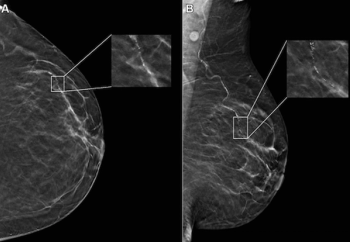

Offering comparable sensitivity to radiologists for detecting contralateral breast cancer on mammography images, an emerging adjunctive AI software may also facilitate earlier diagnosis, according to study findings presented at the at the 2024 American Society of Clinical Oncology (ASCO) Annual Meeting.